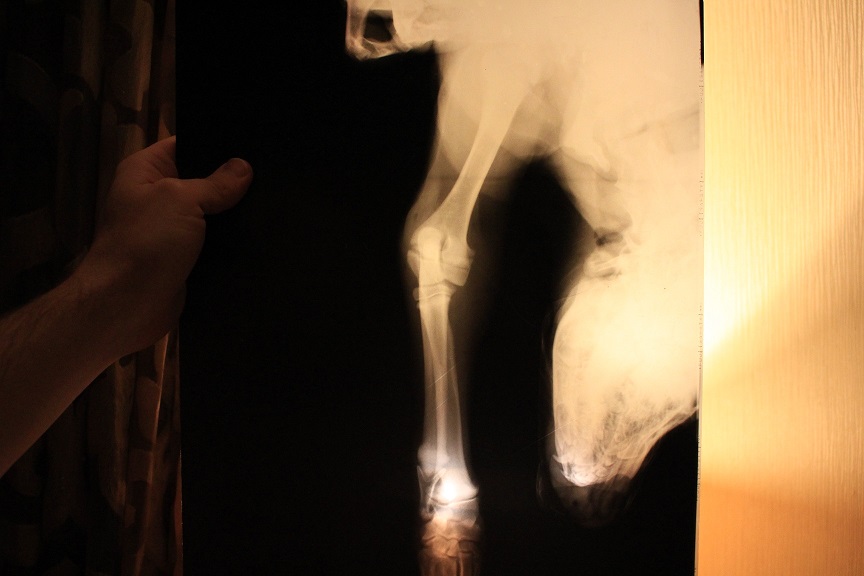

доброго. у нас прокус в месте роста локтевого сустава. локоть работает, а вот запястье на этой лапе болтается (как тряпочка) подскажите, это из-за травмы, или что-то вражденное. до прокуса, все было хорошо

Если до травмы все было нормально - точно не врожденное.

Надо к врачу, проверять чувствительность. Может быть травма нерва, связочного аппарата. Щупать надо.

ходим каждую неделю на контрольный снимок и на консультацию. после травмы прошло 3 недели. чувствительность по всей лапе есть.

врач говорит - нужно время. ждите, попробуйте найти где поплавать.

по неровной или мягкой поверхности она ходит не хромая, опирается на лапу.

только на ровной хромает. на улице бегает, держит этой лапой палочки, может дома просить вкусняшку этой лапой.

это улучшения через неделю после травмы. но меня беспокоит именно мягкость в этом месте. болтается она как сосиска...

Когда запястье болтается, то животное его не контролирует и ставит лапу как бог на душу положит. Обычно на то самое запястье.

На снимках запястье не совсем корректно. Изменений в костной ткани не видно. Да и не наступала бы она.

так она ни когда не наступала. сразу после травмы, просто ее на весу держала. потом только при команде сидеть могла поставить на запястье. когда лежала или в расслабленном состоянии лапа часто была согнута во внутрь. я подходила и расправляла. фиксировать нам не рекомендовали.zver писал(а):Когда запястье болтается, то животное его не контролирует и ставит лапу как бог на душу положит. Обычно на то самое запястье.